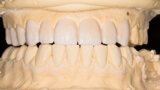

Fig. 25: Final results of the analogue and digital approach.

Fig. 26: Final results of the analogue and digital approach.

Fig. 27: Final results of the analogue and digital approach.

Fig. 28: Final results of the analogue and digital approach.

Fig. 29: Final results of the analogue and digital approach.

Fig. 30: Final results of the analogue and digital approach.

Fig. 31: Final results of the analogue and digital approach.